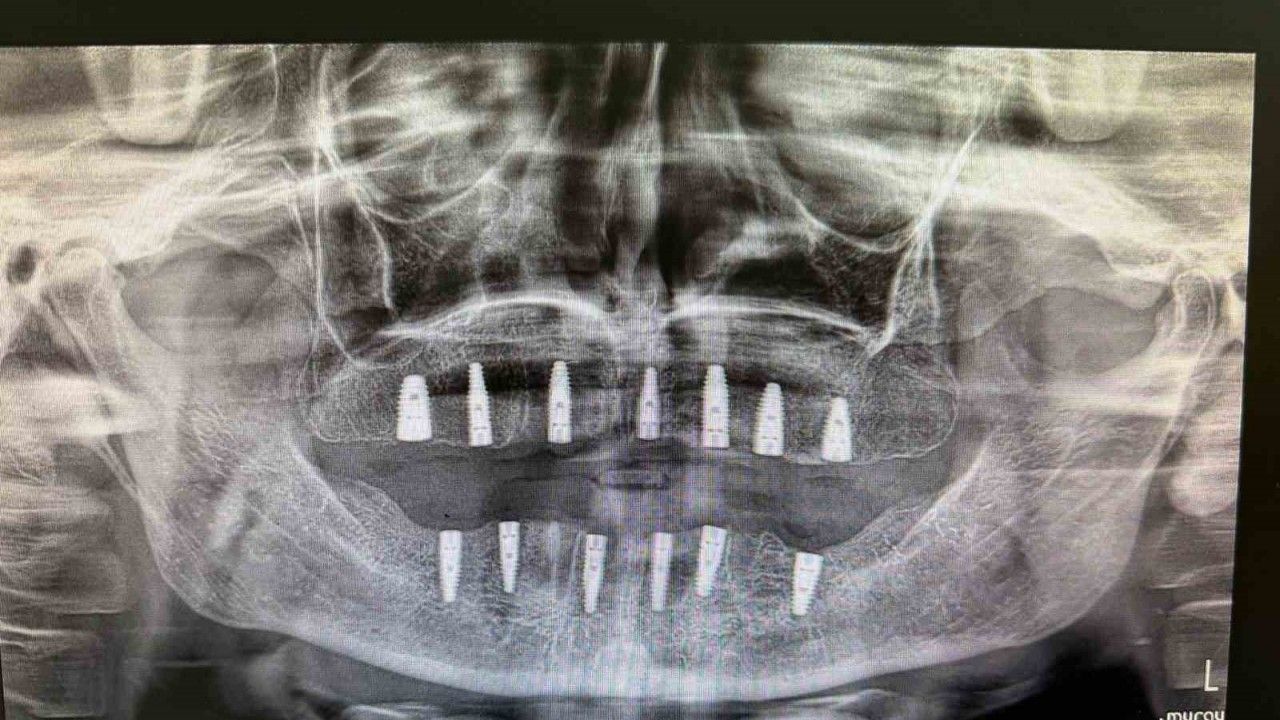

Merkezde görevli Uzm. Dt. Sefa Merve Arıkan tarafından gerçekleştirilen ameliyatta hastaya 13 adet implant yerleştirildi.

Diş implantı, çene kemiğine yerleştirilen ve eksik dişlerin işlevini üstlenen yapay diş kökleri olarak biliniyor. Genellikle dişini kaybetmiş veya hiç dişi bulunmayan hastalara uygulanan bu yöntem, hem estetik görünüm hem de çiğneme fonksiyonunun yeniden kazanılmasını sağlıyor.